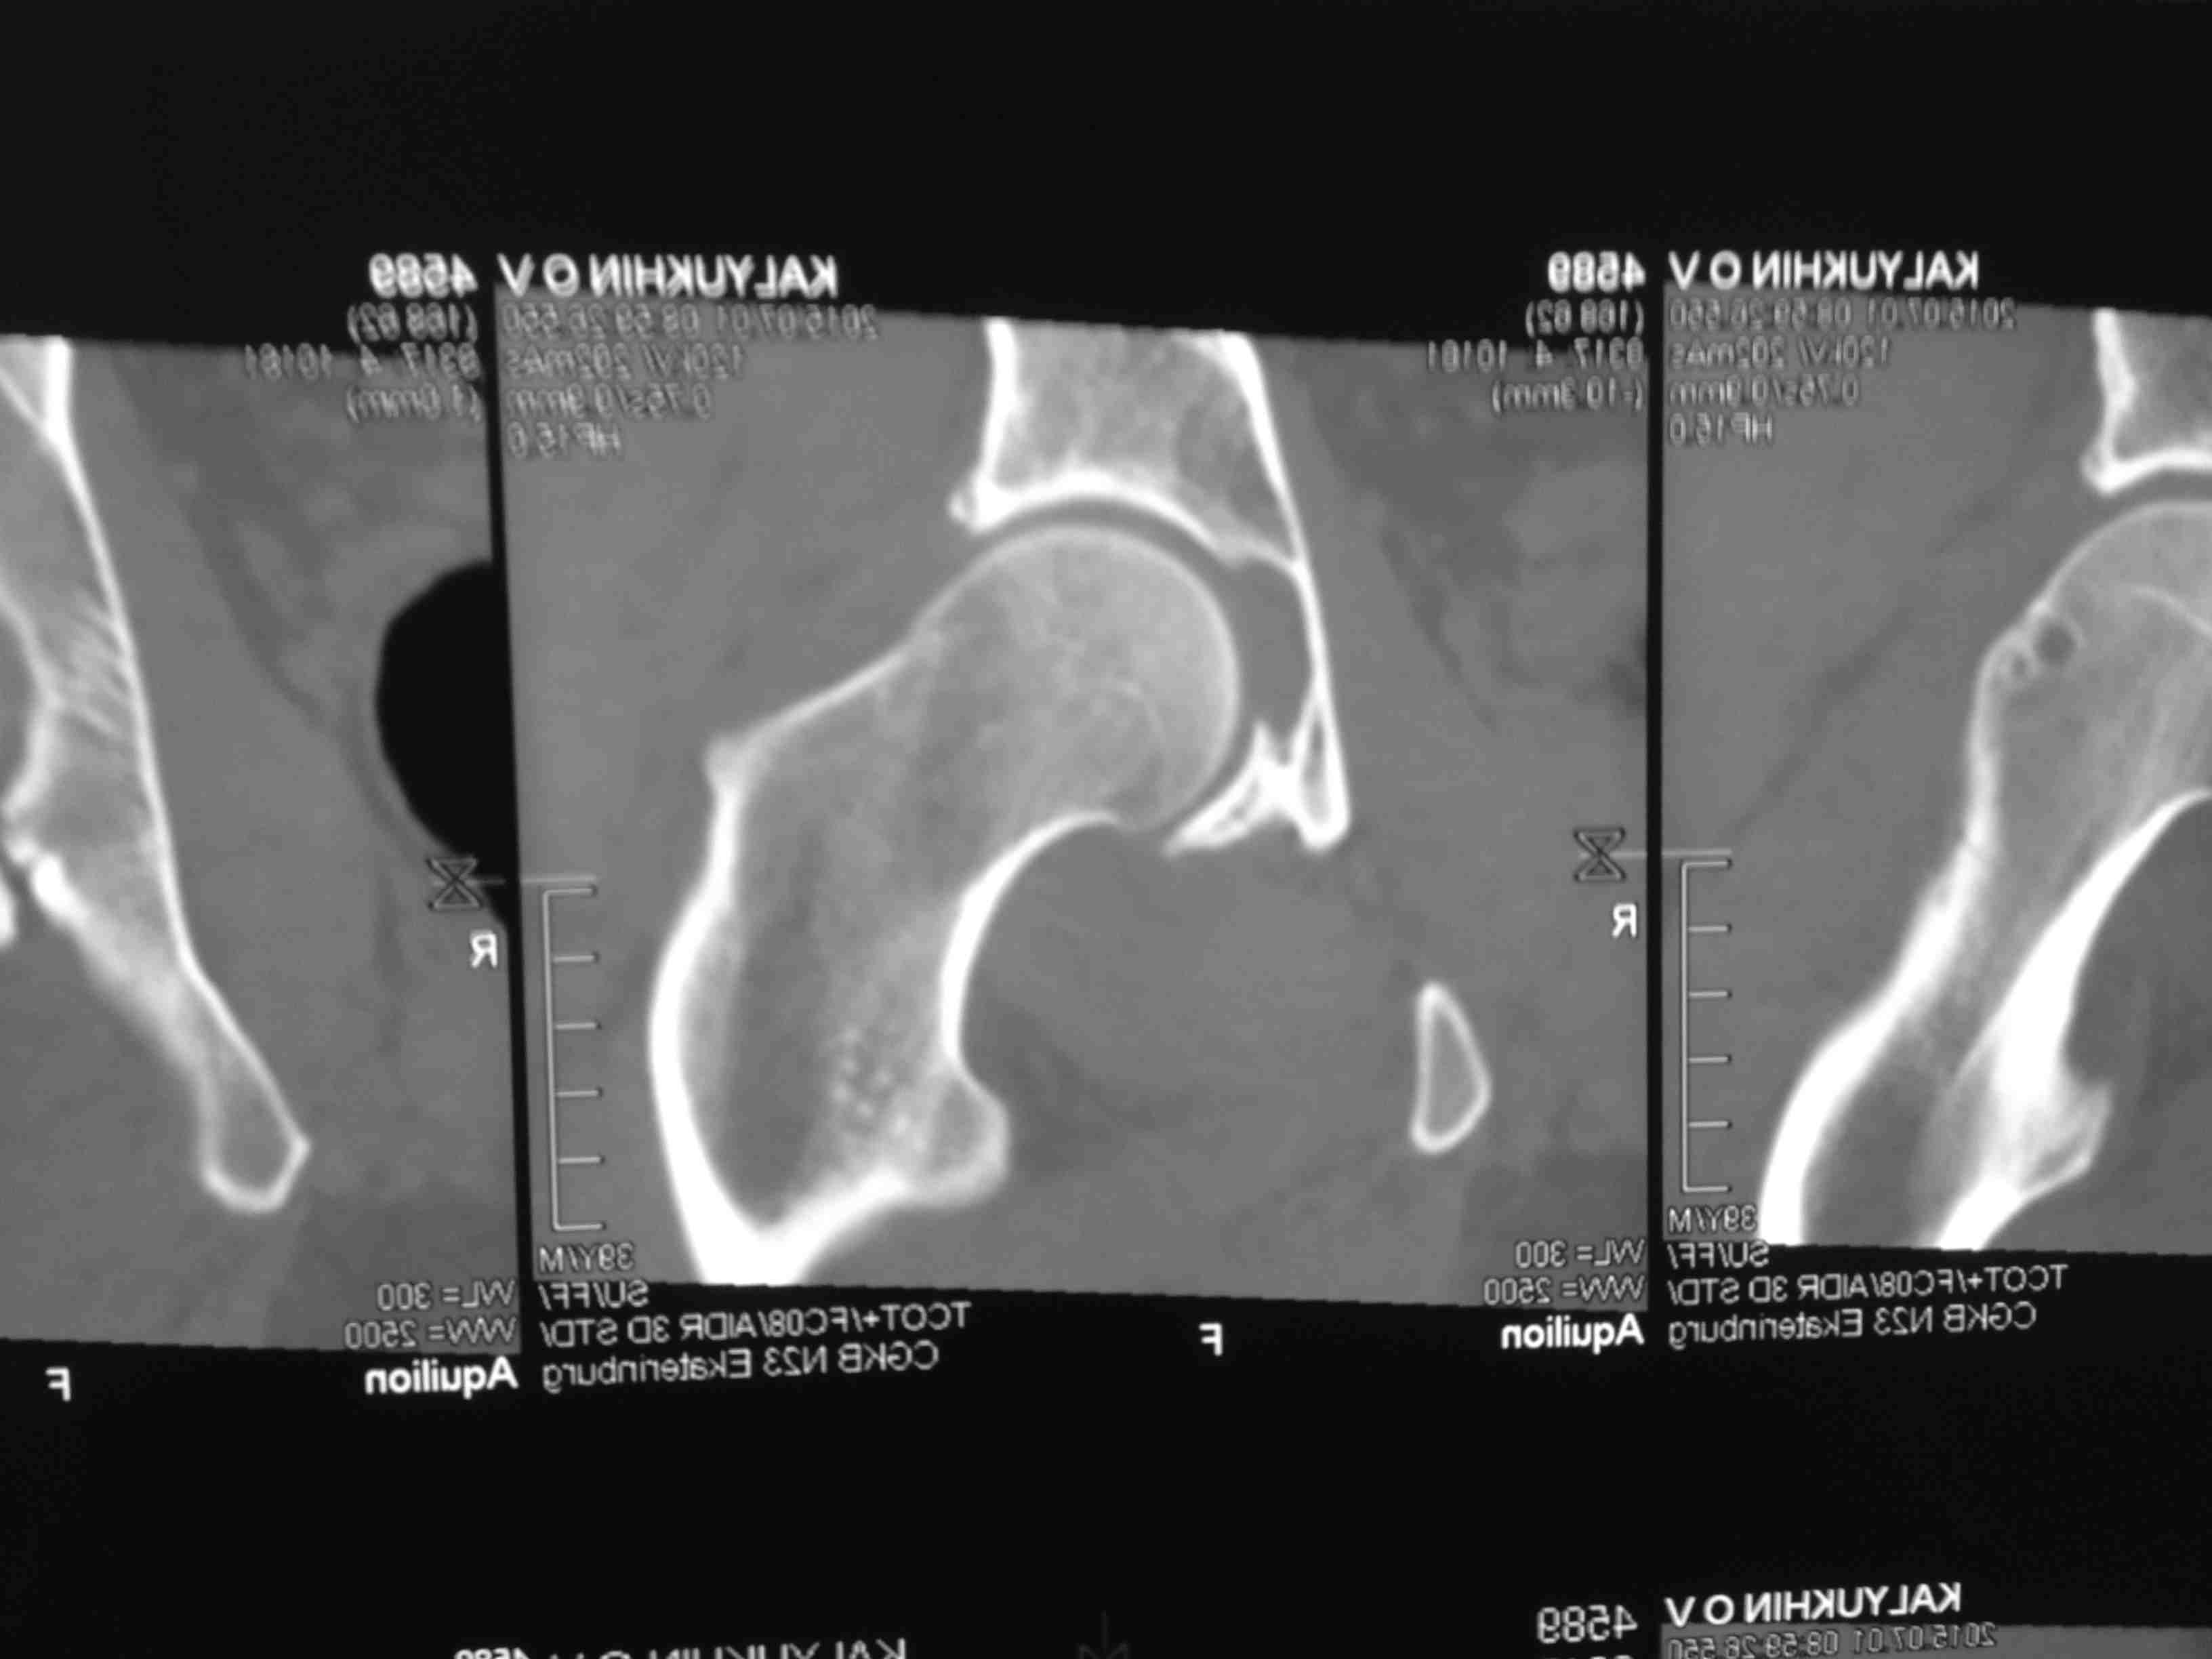

Серия КТ сканов в аппарате

Добрый день, коллеги! Повреждение вертлужной впадины вероятнее всего 62-А1.2 чистый переломовывих, оскольчатый перелом задней стенки, при этом внутрисуставной фрагмент, является частью артикулирующей поверхности ацетабулюм, а следовательно его необходимо извлечь и поместить на место, иначе мозаика может не собраться. Про FAI временно можно не вспоминать (не до него), поскольку наиболее тяжелое повреждение голени требует адекватного вмешательства.На представленных рентгенограммах таза после операции все отлично, полную картину даст КТ.

Голень-41-С3.1 - полный внутрисуставной и метафизарный оскольчатый перелом с доминантным повреждением наружного мыщелка, с импрессией центральной части плато. Первичная тактика полный респект по АО и ОТА. на фоне лигаметотаксиса выполнено КТ, которое четко детализирует повреждение и определяет дальнейшую тактику.

Основная проблема не бугристость, а внутрисуставное повреждение латерального мыщелка с импрессией центральной части. С большей вероятностью, есть паракапсуллярное продольное повреждение наружного мениска.